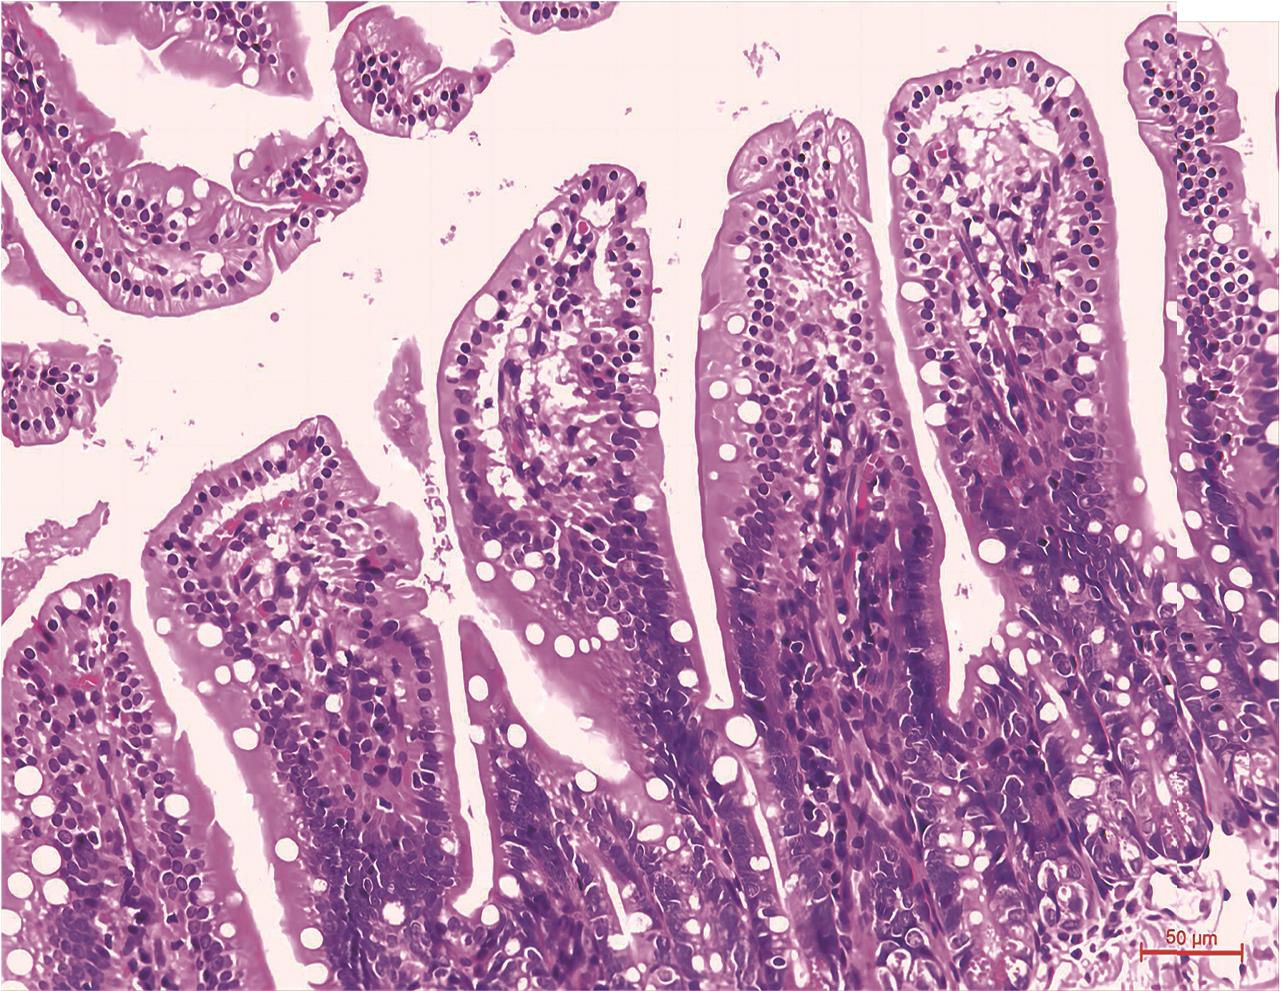

• Maresin1通过Sirt1抑制Caspase11/GSDMD通路减轻小肠缺血再灌注损伤的研究

摘要:目的 探讨巨噬素1(Maresin1,Mar1)在小鼠肠缺血再灌注(ischemia-reperfution,IR)中的作用及其可能机制。方法 通过夹闭肠系膜上动脉(superior mesenteric artery,SMA)建立小肠IR模型。第一部分①组12只小鼠随机分为Control组、IR组和IR+Mar1组。第二部分②组20只小鼠随机分为Control组、IR组、IR+Mar1组、IR+EX527组、IR+Mar1+EX527组。Mar1于术前30 min采用5 μg/kg腹腔注射。EX527于术前1 d 10 mg/kg经腹腔注射。Control组仅分离SMA而不夹闭。其余模型组均用无损伤血管夹夹闭SMA根部,45 min后松开血管夹形成小肠IR模型。各组小鼠均于再灌注后4 h采集静脉血和回肠标本。检测①组小鼠肠组织超氧化物歧化酶(superoxide dismutase,SOD)、丙二醛(malondialdehyde,MDA)、谷胱甘肽(glutathione,GSH)含量;检测血清4 kd荧光素异硫氰酸酯-葡聚糖(FITC-Dextran 4000,FD-4)含量;免疫荧光染色检测肠Occludin蛋白表达,HE染色观察肠组织病理形态。Western blot检测①、②组肠组织Sirt1、P-NF-κB p65(P-p65)、Caspase11、GSDMD-N蛋白表达。结果 ①组中与Control组相比,IR组肠组织MDA水平,血清FD-4含量,病理学损伤程度均升高(P<0.01);SOD、GSH水平,Sirt1蛋白表达下降;P-p65、Caspase11、GSDMD-N蛋白表达增加。与IR组比较,IR+Mar1组肠组织MDA水平及血清FD-4含量,病理组织学损伤程度均下降(P<0.05);SOD、GSH水平,Sirt1蛋白表达增加;P-p65、Caspase-11、GSDMD-N蛋白表达减少。②组中与IR+Mar1组比较,IR+Mar1+EX527组Sirt1蛋白表达下降;P-p65、Caspase11、GSDMD-N蛋白表达增加。而IR+EX527组与IR+Mar1+EX527组蛋白表达差异无统计学意义。结论 Mar1预处理通过Sirt1抑制Caspase11/GSDMD通路减少肠组织缺血再灌注损伤。